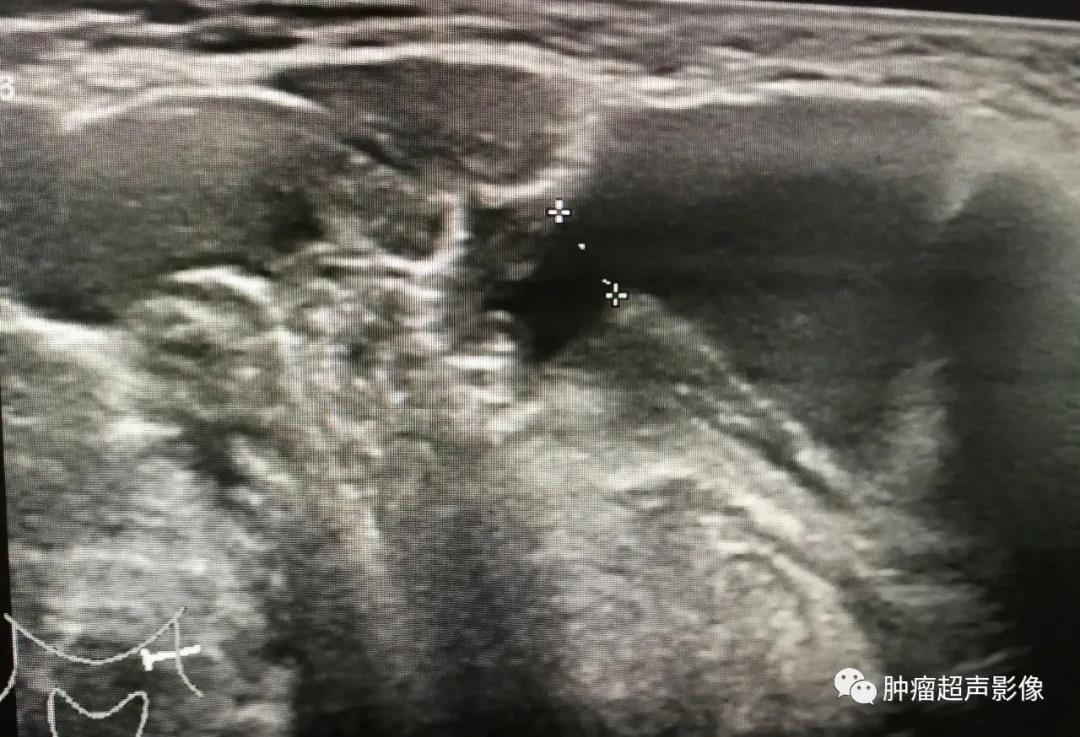

手术证实的口外型舌下腺囊肿:颌下区不规则无回声向口底部延伸,下颌舌骨肌有缺损,边缘毛糙,无明确的包膜,透声佳,无血流(来自微信好友会诊病例)。